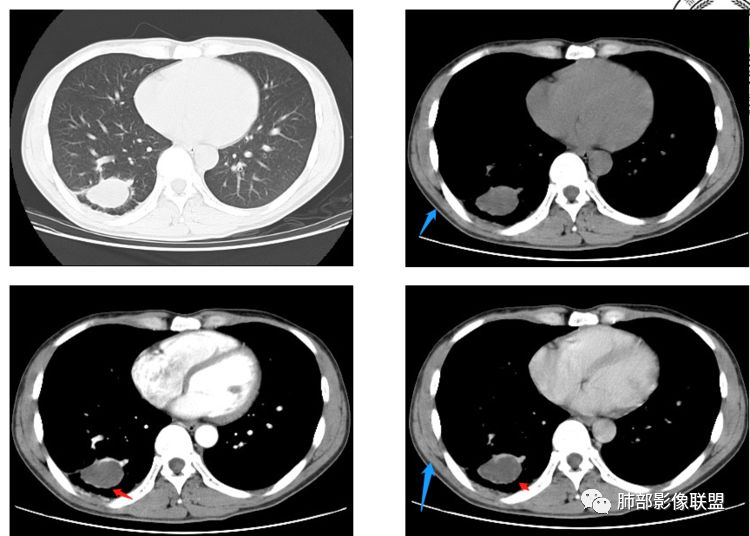

小赵:青年男性,慢性咳嗽,低热,血沉略快。右肺类圆形肿块,密度偏低,周围见条索,较低层面似见卫星灶,邻近胸膜增厚。增强扫描薄膜样强化。综合考虑结核可能

市医院-时建文:青年男性,慢性咳嗽,低热,右肺类圆形肿块,密度偏低,周围见条索,血管贴边,邻近胸膜增厚。结核?psp?

一米阳光:右肺下叶后基底段长圆形病变,边缘清晰,中心部密度减低,增强病变前缘见血管影,略环形强化,病变周围见点状及索条影,结合年轻病史,考虑结核

甄德强:右肺下叶结节影,边缘见多条软毛刺,包膜样强化,卫星病灶,考虑结核,不除外合并曲霉

大雄:似乎是支气管相连续,无强化,平扫似有高密度,考虑支扩粘液栓(曲霉所致)

小微:青年男性,慢性咳嗽,低热,血沉快。右肺类圆形肿块,其内见低密度影,周围见条索,较低层面似见卫星灶,邻近胸膜增厚。增强扫描薄膜样强化,其内为低密度坏死。综合考虑结核可能。有血管贴边,待除外PSP

弹指之间:1. 青年男性,慢性咳嗽,低热,血沉快。2. 右肺下叶类圆形肿块,周围见条索,较低层面似见卫星灶,邻近胸膜增厚。增强后见轻度延迟强化,见血管贴边征,肺门侧见小淋巴结影(肺静脉起始处肿大淋巴结不确切);3. 右肺下叶体积未见缩小,局部支气管不扩张,无钙化;综合考虑结核可能,PSP和小细胞肺癌待排

看图说话:肿块边缘清晰,中心密度减低,环形强化,见血管贴边,周围见卫星灶,临近胸膜受累,结合病史年轻,血沉快,考虑炎性病变,考虑结核,周围有高密度索条,粘液栓,不除外隐球。有血管贴边,但位置偏胸膜,排除PSP

heronsbill:增强强化不明显,周边可见血管绕行,粘液表皮样癌,不能除外;

崇军:右肺下叶肿块影,形态不规则,边缘清晰,中心密度减低,环形强化,见血管贴边,周围见卫星灶,临近胸膜受累,结合病史年轻,血沉快,考虑炎性病变,考虑结核,但有血管贴边,外围分布,周围有晕,虽然男性,所以PSP待排

春秋:年轻男性,慢性病史,右下肺多发病变,卫星灶,环形强化,考虑结核可能性大

百事可乐:右肺下叶占位,首先良性病变,局灶性机化性肺炎、结核,PSP需要鉴别。病灶特点:右肺下叶类圆形肿块,病灶邻近支气管无狭窄及扩张,其内密度较低,液化坏死,无明显强化,可见长毛刺、条索、卫星灶,周围见肺气肿征象、血管贴边,临近胸膜增厚

可芸:青年男性,慢性咳嗽,低热,右肺类圆形肿块,密度偏低,邻近胸膜反应性增厚。增强扫描薄膜样强化。综合考虑结核球,鉴别PSP

马春平:曲霉菌 鉴别:结核、肺脓肿。青年男性,刺激性咳嗽病史迁延半年,低密度无強化、边缘血管征,周围长柔毛刺伴少量结节、临近胸膜反应增厚

张帅:患者青年男性,间断性咳嗽伴右胸反复不适半年。胸CT:右肺下叶后基底段实性病灶,边缘光滑,分叶,气管血管贴边,增强病灶内可见强化,病灶周围可见结节样改变,病灶周围胸膜明显增厚,考虑慢性感染:TB?,鉴别PSP?

秋实:青年男性, 病史半年,低热伴胸痛,右肺下叶肿块,多房分隔强化,周围见支气管绕行,邻近胸膜增厚牵拉,周围不干净,考虑慢性感染性疾病:结核,慢性化脓性改变伴胸膜炎。囊肿伴感染

玫:男,34岁,间断咳嗽伴右胸不适,低热右肺下叶见类圆形肿块影,边界清晰,边缘见毛刺及长条索影,其内密度不均匀,增强扫描似见血管贴边征,结合年龄先考虑结核,不除外PSP?

果豆:男,31岁,咳嗽,低热,右肺下叶一结节,边缘光滑,与胸膜牵拉,如果纵膈窗是环形强化,结核球可能性大。如果是血管贴边考虑psp

小强:青年男性,低热,右肺结节,分叶毛刺,部分边缘光滑,周围有散在斑片,增强周围线样强化,考虑良性,结核

晨:青年男性,慢性咳嗽,低热,右肺类圆形肿块,周围卫星灶,增强扫描边缘强化,考虑结核球可能,有血管贴边,鉴别PSP

男,34岁,主诉:间断性咳嗽伴右胸反复不适半年;现病史:右胸不适,深呼吸加重,伴轻度咳嗽、低热;

青年男性、病史半年,低热;

右肺下叶囊性病变,边缘光滑,薄环状强化,内壁较光滑

血管贴边

周围多发长索条

远端有斑片状条带状高密度影,周围肺气肿

附近胸膜增厚,内有血管影